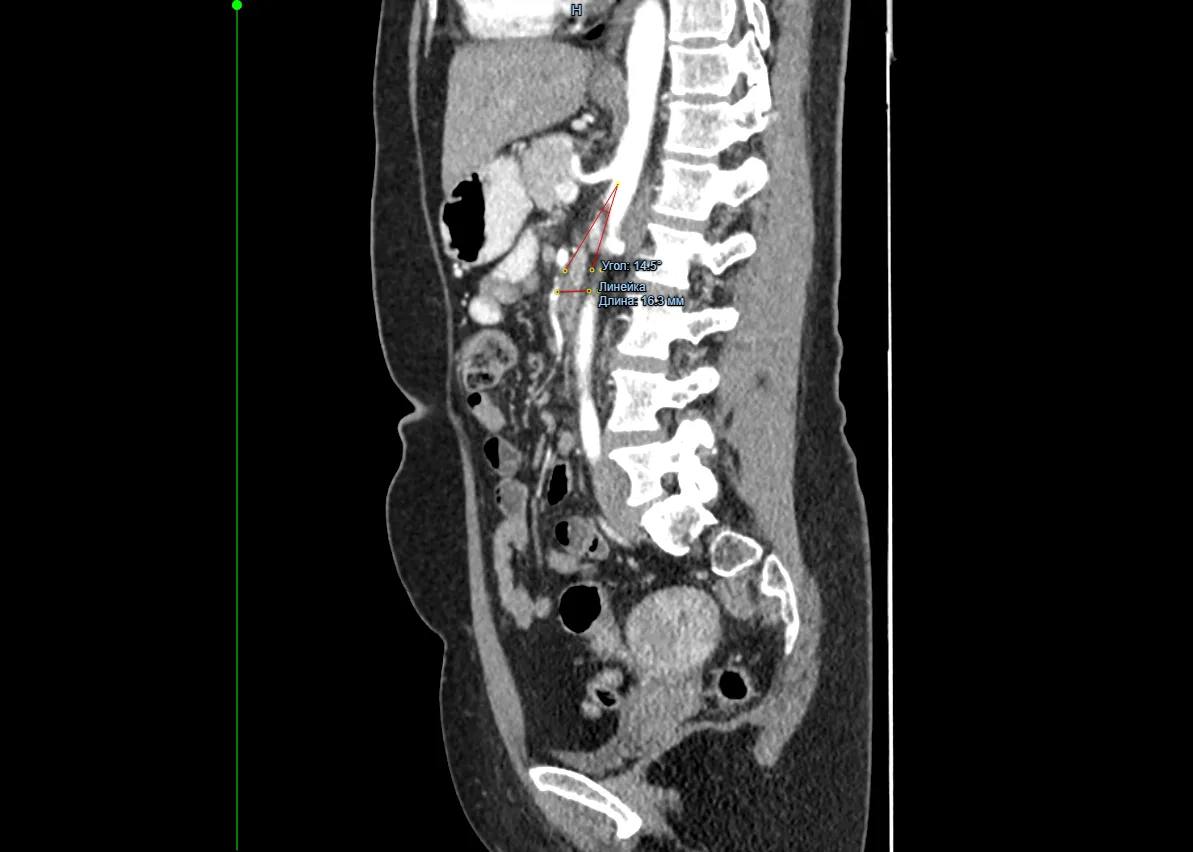

Врачи хирургического отделения №3 Красноярской межрайонной клинической больницы №20 им. И.С. Берзона провели операцию 49-летней пациентке с синдромом Уилки. Из-за него женщина долго не могла нормально питаться и сильно похудела.